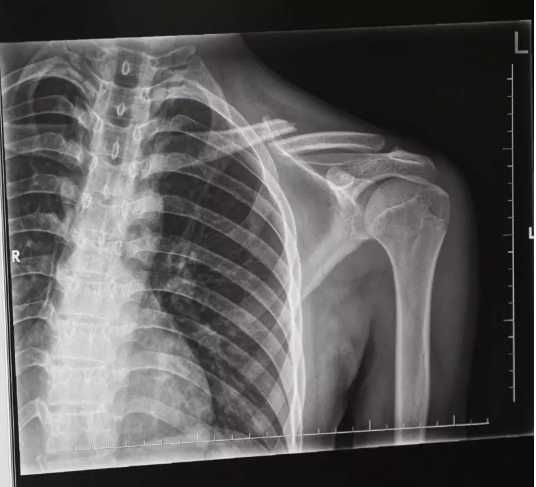

随后,马某某带着年轻男子来到杨庙镇医院检查,经拍X光片,医生诊断这名自称“丁某某”的伤者锁骨骨折,需要手术。见此情形,与“丁某某”同行者以两人无法做主为由,致电一位自称年轻男子亲戚的人。后再与这位亲戚上商量中,其以小伙不是本地人,需要回老家做手术为由,最终让马某某赔偿了一万元。过了一段时间,马某某越想越觉得可疑,3月28日,他拨打110报了警

随后,警方对周边城市所有医院在最近的拍的X光片进行核查,发现3月17日至4月7日间,在寿县、凤台、长丰、肥西的多家医院均有名为“丁某某”的锁骨骨折的X光片子。后经过监控录像辨认,发现“丁某某”均为同一人,且均无治疗情况。据此警方认定这是一个碰瓷团伙,于是成立专案组。

“因为拍片可以看出新伤还是旧伤,所以该团伙每雇一个小伙,就利用愈合前的十天内疯狂作案,等到伤口开始愈合后就换人。”办案民警告诉记者,在这十天的时间内,他们选择市郊或县城附近监控较少地区,疯狂作案。而受雇的小伙,基本都是在广东打工,受到每次4、5万元的高额利润的诱惑选择铤而走险,成为了曾某某、何某某等人诈骗的工具。